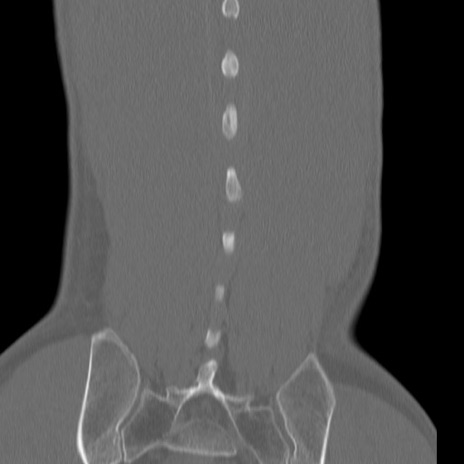

腰椎CT

3D再構成